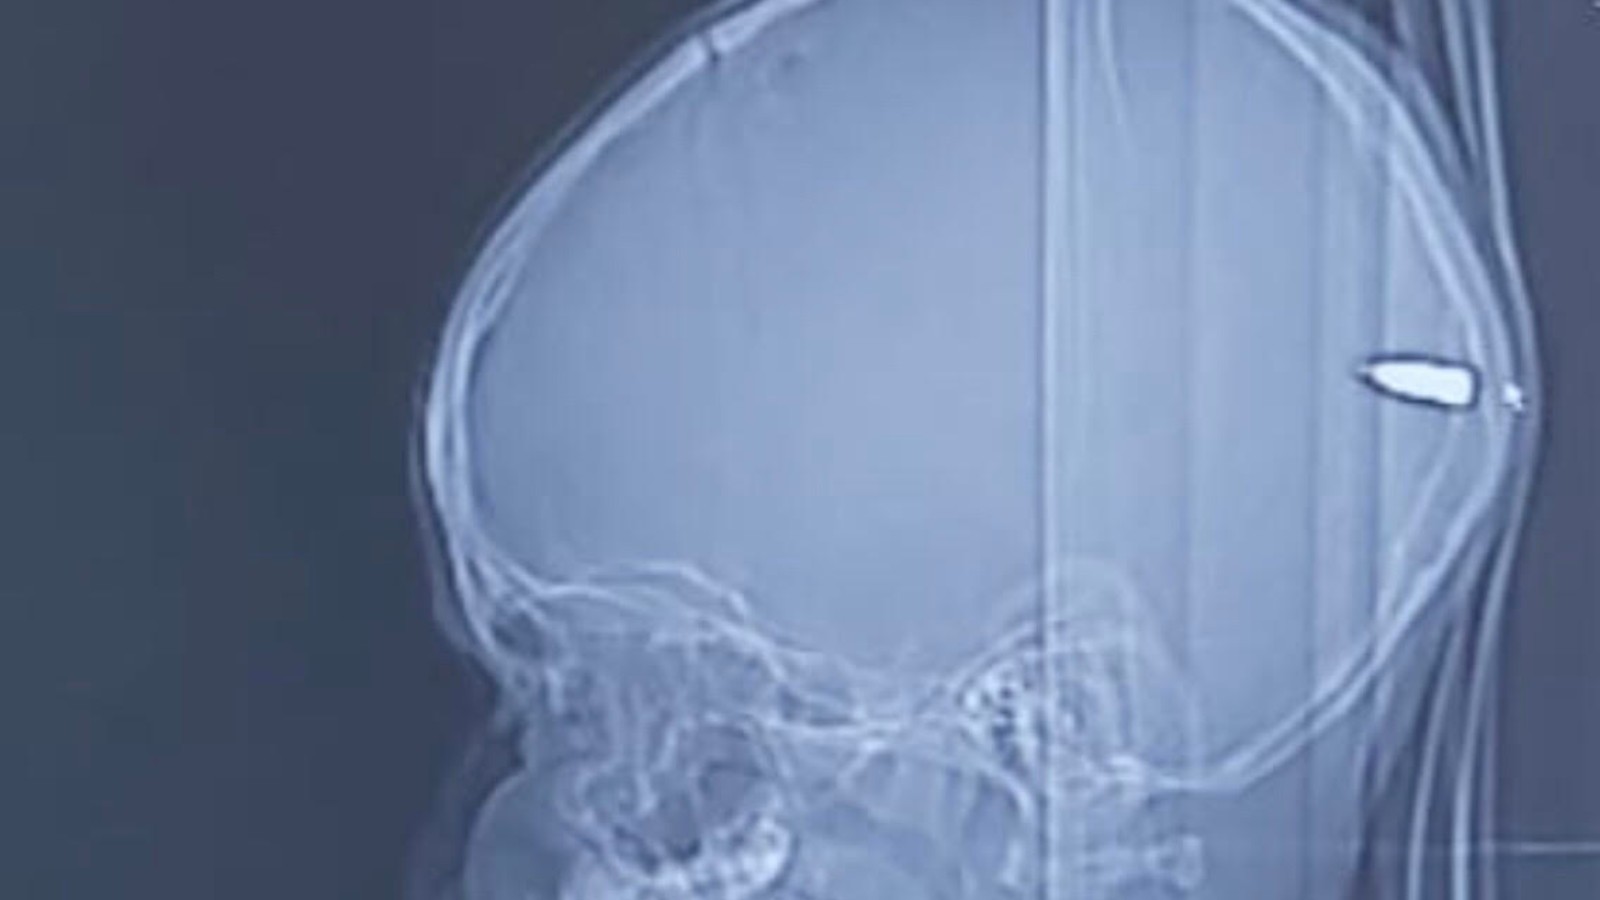

He was rushed to Hadassah University Medical Center, where a CT scan showed that a 3/4-inch, heavy bullet penetrated his skull from the right side. It tore a path through his brain and stopped, lodged just inside the left side of the boy’s skull.

With the help of ultrasound and X-rays, they discovered the bullet had receded several inches into his brain. It was in the occipital lobe, which includes the visual cortex. Its route from entry included parts of the brain responsible for motor skills, behavior and higher thought, just missing major arteries and veins by a tenth of an inch.